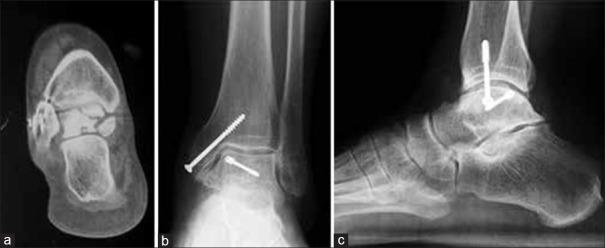

Six patients with talar malunions or nonunions who underwent surgical treatment were reviewed in this retrospective study. There were three nonunions and two malunions of the talar body and one malunion of the talar neck. Clinical evaluation included all the parameters used in the American Orthopaedic Foot and Ankle Society (AOFAS) hindfoot scale. Arthritic degeneration of the ankle joint was assessed according to a modified Bargon scale.

The mean followup was 86 months (range 24-282 months). There were no cases of postoperative avascular necrosis of the talus. Four of the six patients in our series required a subtalar fusion as part of the reconstruction procedure. The average preoperative AOFAS hindfoot score was 34, and at the time of the last evaluation, it was 74. The mean preoperative score on the modified Bargon scale for the tibiotalar joint was 1.17. At the last followup, it rose to 1.33. Three different deformities of the talus were identified (a) flattening of the talus (b) extra-articular step and (c) intraarticular step.

平均随访86个月(范围24 - 282个月)。无距骨术后缺血性坏死病例。我们系列中的6例患者中有4例在重建手术中需要进行距下关节融合。术前AOFAS后足平均评分为34分,在最后一次评估时为74分。改良巴尔贡量表中胫距关节术前平均评分为1.17分。在最后一次随访时,升至1.33分。确定了距骨的三种不同畸形:(a)距骨扁平;(b)关节外台阶;(c)关节内台阶。